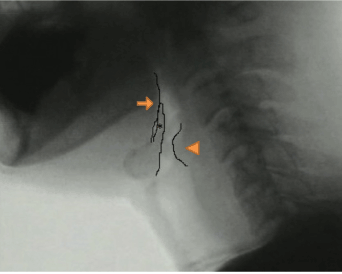

From the viewpoint of the neoglottis morphology, prior to swallowing initiation, the arytenoid cartilages sit on the cricoid cartilage and are already located in an elevated position due to the pexis procedure. Furthermore, in the case of post-SCL swallow, we frequently found that the valleculae were not easily identifiable due to epiglottic approximation to the root of the tongue. These features appeared to make it easier for the arytenoid to make contact with the tongue base (Figure 3). Thus, by the time the bolus has arrived at the PES, the tongue base (attached to the epiglottis) is seen to approximate the arytenoids effectively and rapidly to close the supraglottic passage (Figure 4). Moreover, the supraglottic airway remains closed until after the PES has opened (Figure 5). These findings, which are consistent with the report by Woisard et al. [17], were demonstrated by the prolonged duration of airway closure and PES opening.

Figure 3. Retrofluorographic lateral view at bolus-hold position, showing an open airway. The arrow, arrowhead, and asterisk show the tongue base, arytenoid, and epiglottis, respectively